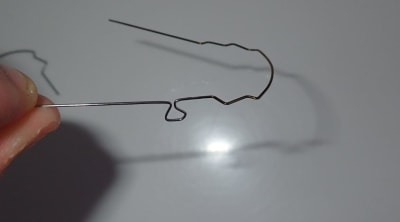

Un exemple d'usage du traitement thermique.

Cas lingual, on à eu un effondrement de la molaire dans l'espace d'extraction . Ici soucis si j'utilise un fil niti continue je vais avoir des effet secondaire sur la prémolaire, utiliser un uprighting spring serait bien sur idéal mais en lingual pas évident à mettre en place .

Avec un SS on peut faire des boucles mais seul soucie en lingual pas évident de faire de grosse bouche car on touche rapidement le palais. Of course un très bon plieur peut s'en tirer mais je ne suis pas un dieux du pliage de fil.

Ici j'ai plié un arc SS 16 22 classique et ai fait une petite boucle ( notez que malgré la taille réduite l'on pouvais difficilement faire plus gros. Puis traitement thermique du file jusqu'a la boucle. Résultat mon file devient plus rigide en sur la partie qui n'est pas censé bouger. Mécaniquement ça équivaut à augmenter la taille de la boucle.